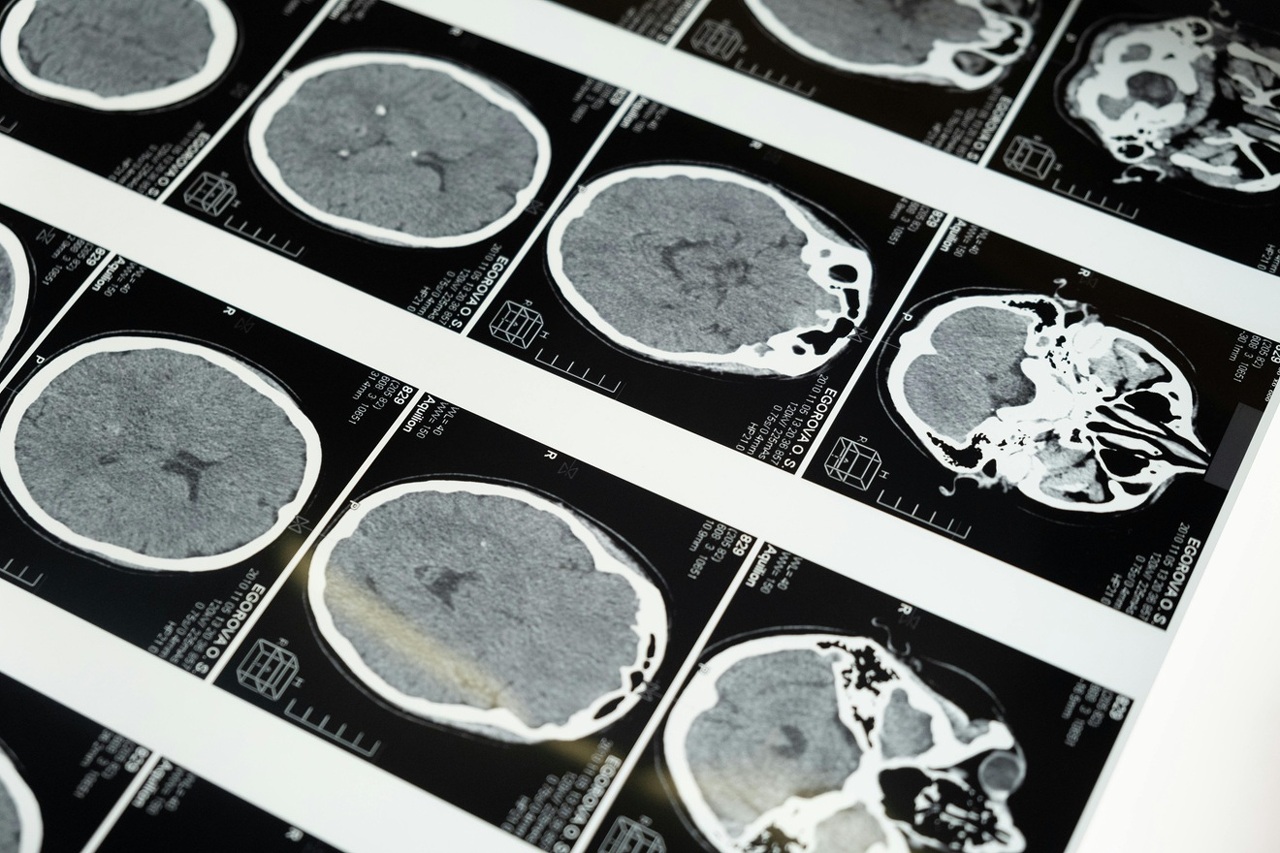

Zahvaljujući novom financiranju, istraživački tim planira mapirati veze između senzornih neurona i unutarnjih organa, uključujući srce i probavni sustav. Cilj im je stvoriti prvi svjetski atlas unutarnjeg osjetilnog sustava.

Dosadašnja istraživanja pokazala su da poremećaji u živčanim putovima mogu biti povezani s različitim stanjima, uključujući autoimune bolesti, kroničnu bol i visoki krvni tlak.